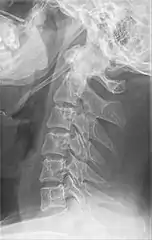

Anteroposterior and lateral radiographs of cervical spine showing ossification of the stylohyoid ligament on both sides

Imaging is important and is diagnostic. Visualizing the styloid process on a CT scan with 3D reconstruction is the suggested imaging technique.[12] The enlarged styloid may be visible on an orthopantogram or a lateral soft tissue X ray of the neck.